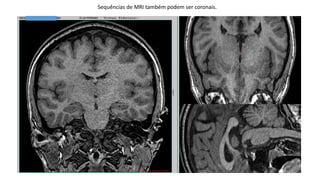

Sequências de MRI também podem ser coronais.

Sequências de MRItambém podem ser coronais.